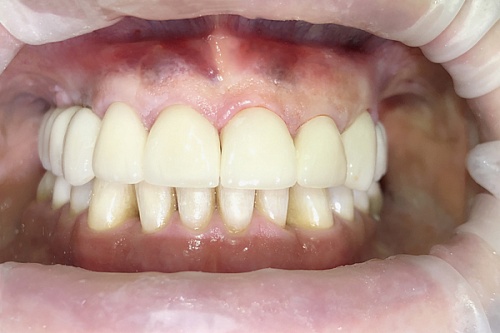

Сохранить зубы и пародонт помогает правильная гигиена полости рта дома и в кресле стоматолога, а также своевременное протезирование и имплантация, которые замещают удаленные зубы и равномерно распределяют жевательную нагрузку, не позволяя костной ткани атрофироваться.